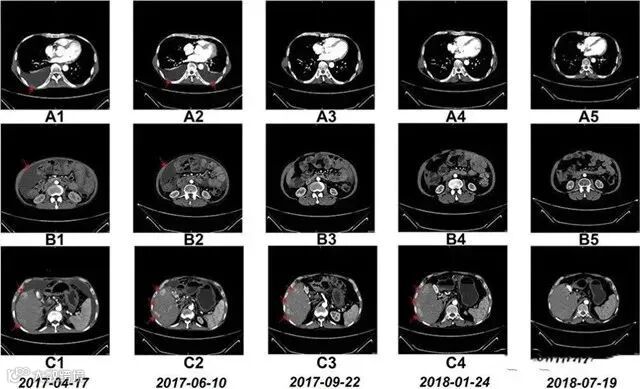

△NK细胞治疗前和治疗期间的CT扫描结果

案例2

国内一名60岁的卵巢癌晚期患者,在接受了体外扩增,高度活化的同种异体NK细胞的临床治疗后,CA125水平从11,270降至580,所有腹水都消失了。此外,CT扫描的肿块体积减小,并且没有出现副作用。

案例3

一名广泛期小细胞肺癌患者,在进行4个疗程化疗和4次高度活化NK细胞回输后,患者第一次进行治疗后的CT复查,结果显示,肿瘤缩小到了原来的1/8。而且距发病第六年的CT复查中,仍旧没有发现任何异常及复发的迹象。